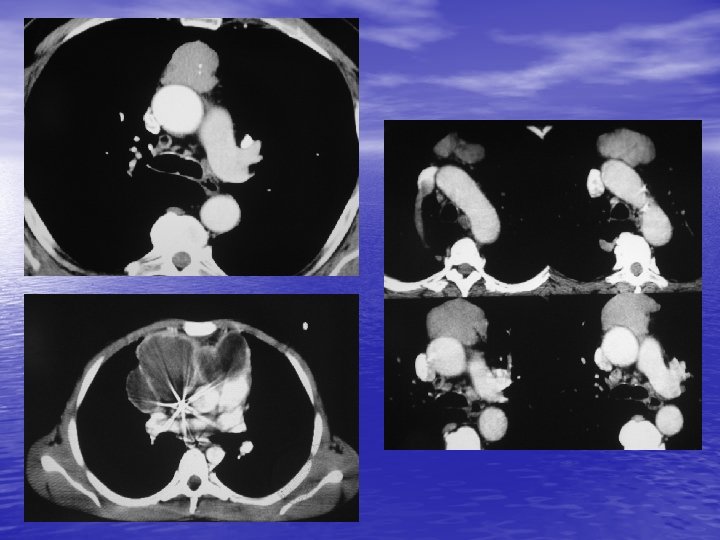

2. 2. TDM - Reconnaissance de la nature vasculaire d’une masse médiastinale. - Détection de petites tumeurs (supérieure au cliché rx thoracique). - Localisation des tumeurs : 8 compartiments. - Reconnaissance du contenu de la tumeur : hypervascularisation (goitre, thymome, adénome parathyroïdien, paragangliome, …) calcifications inconstantes (goitre, ADP, thymome, tumeurs nerveuses, …), liquidiennes (kystes dérivés de l’intestin primitif, lymphangiome, thymome), graisseuse (lipome, liposarcome).

- Recherche de signes de malignité : lésion mal - limitée, densification de la graisse. Bilan préopératoire. Guidage d’une biopsie.

6. ADENOPATHIES MEDIASTINALES - Etiologie n° 1 des masses du médiastin. - Bénigne ou maligne. - Sarcoïdose : caractère symétrique. - Lymphome malin (Hodgkin, LMNH : caractère asymétrique). - Métastases : ++ cancer bronchique. - Surtout médiastin moyen.